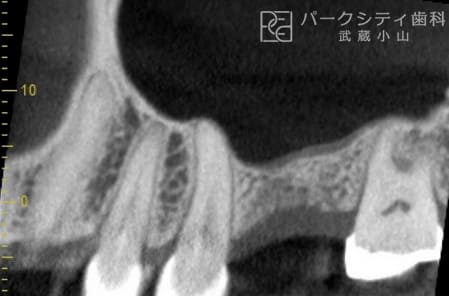

上顎洞挙上術にて骨の高さを確保し、インプラント治療した症例

- 上顎洞挙上術

インプラント埋入

顎骨が足りなく他医院でインプラント治療を断られた方のケースです。上顎洞挙上術を用いて顎骨を確保し、インプラント治療をおこないました。